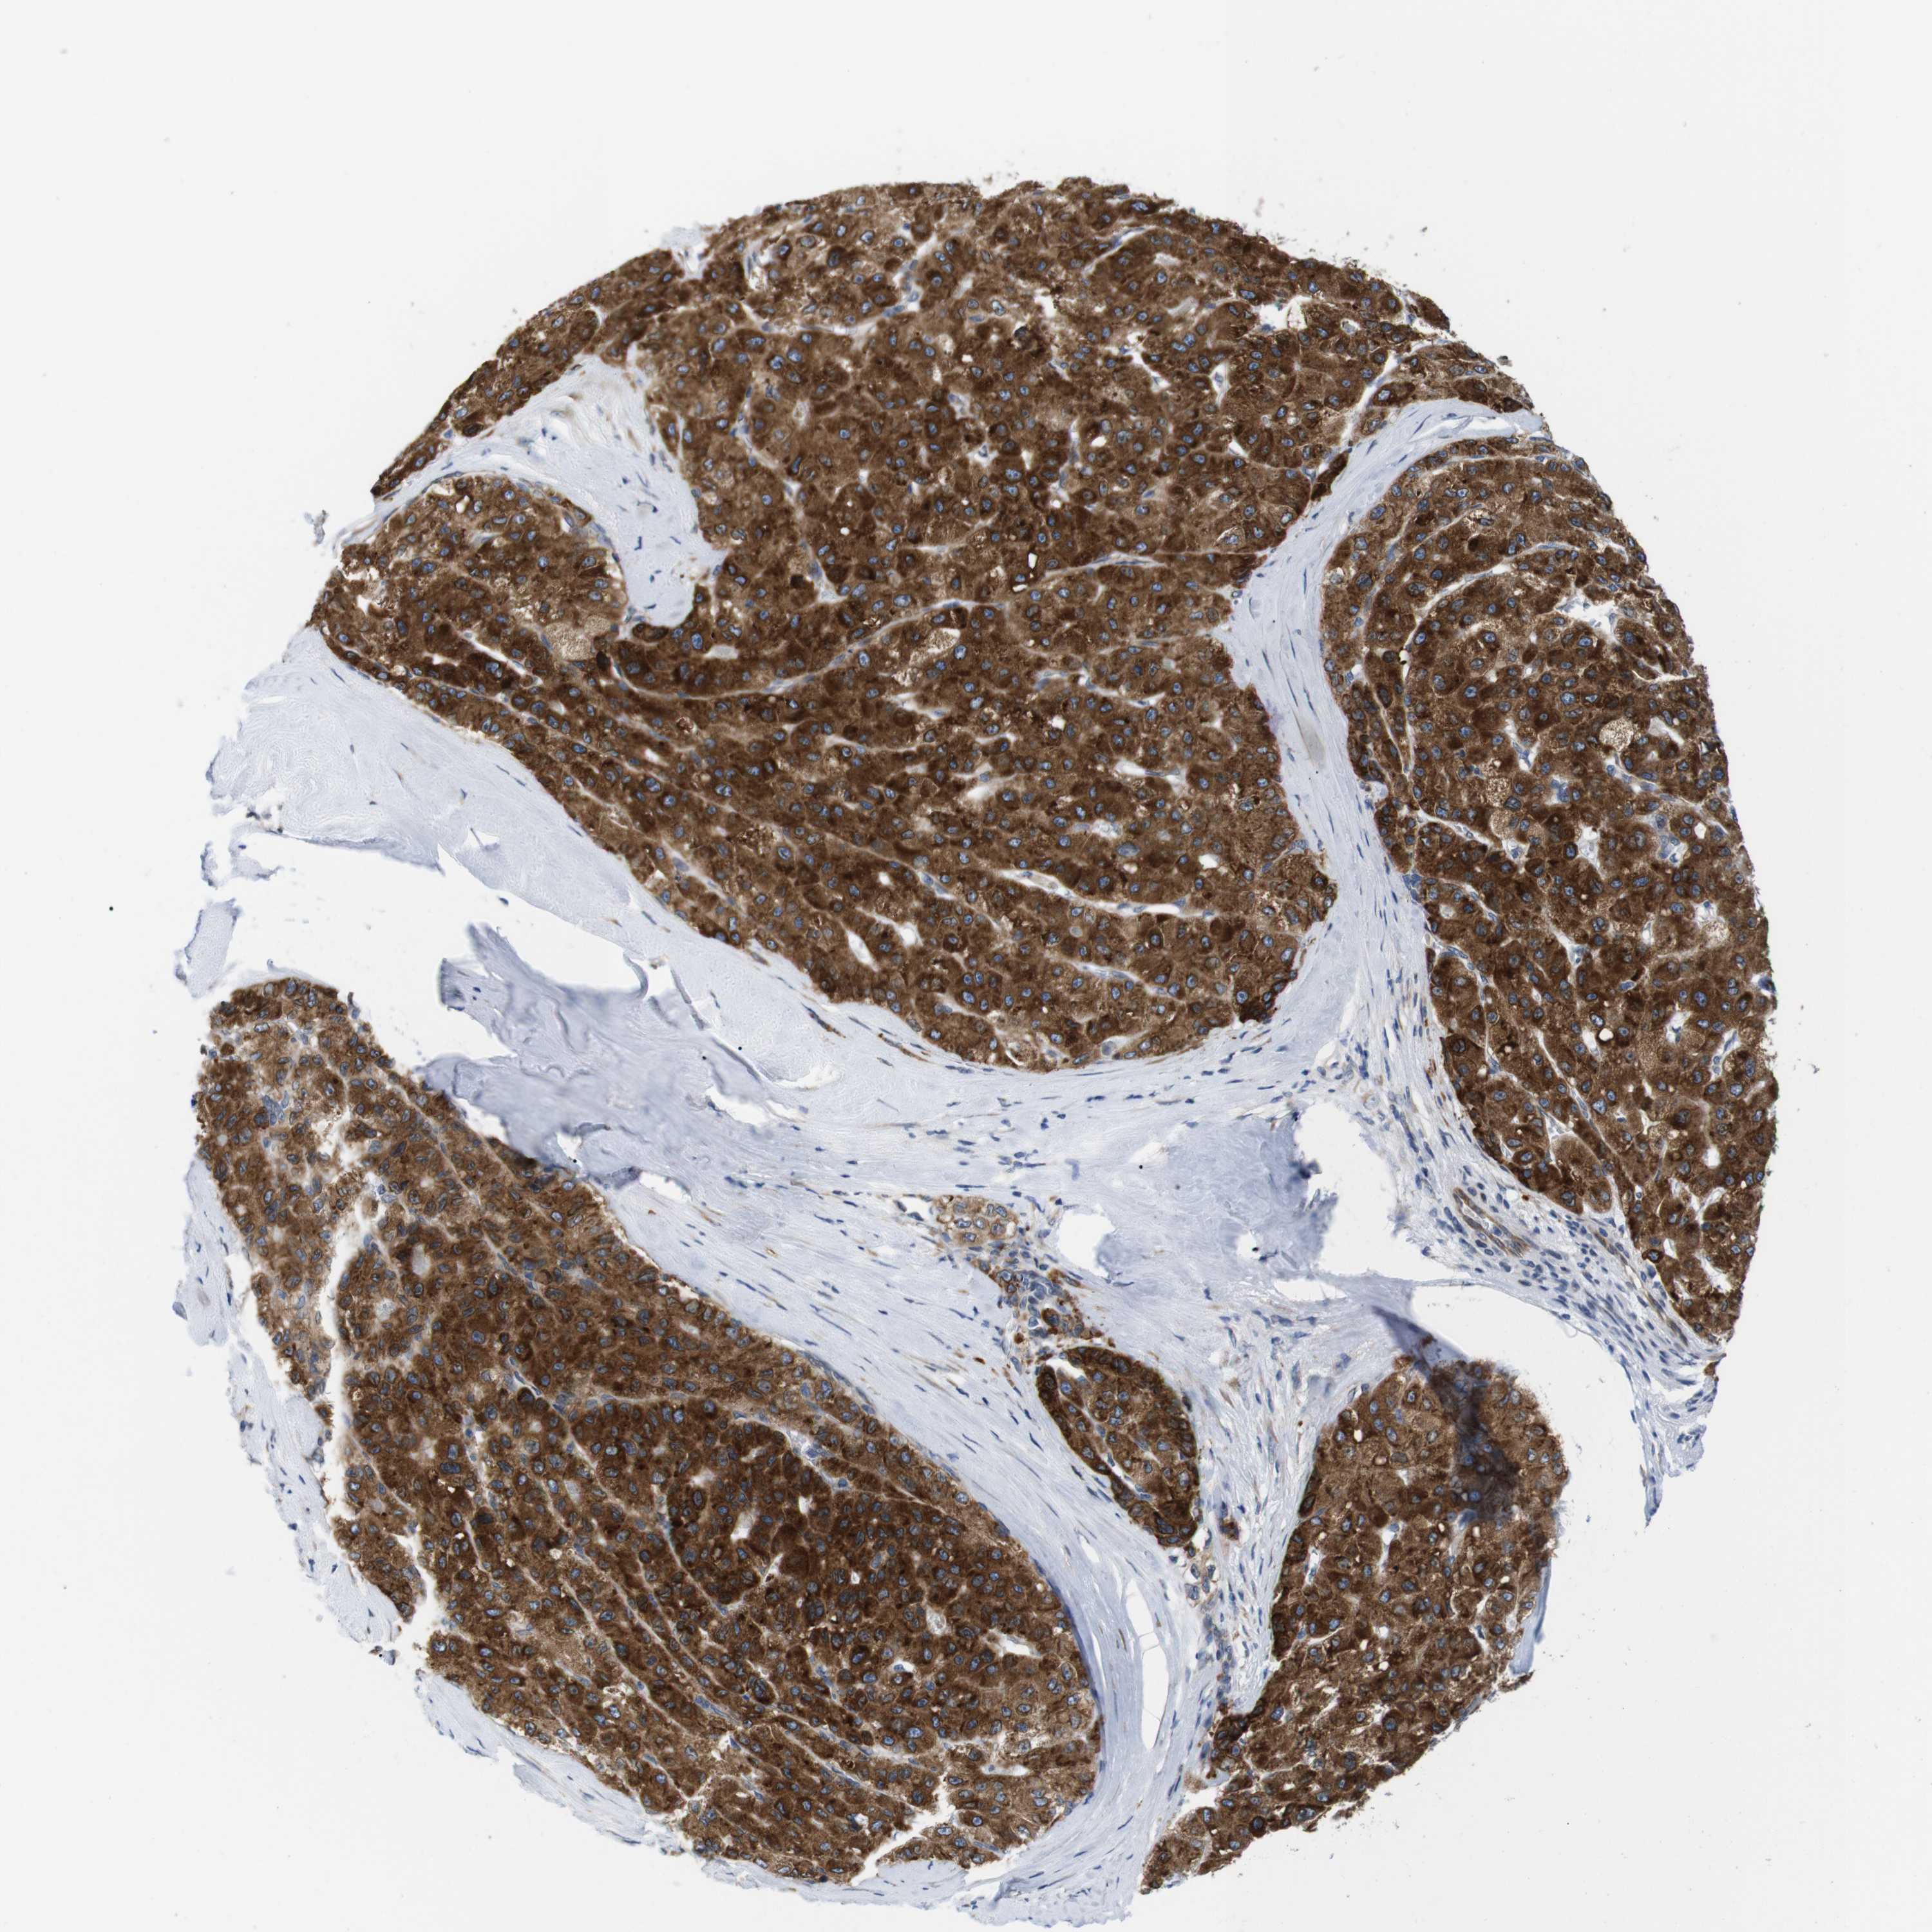

LIVER CANCER - Protein expressioni

A mouse-over function shows sample information and annotation data. Click on an image to view it in a full screen mode. Samples can be filtered based on level of antibody staining by selecting one or several of the following categories: high, medium, low and not detected. The assay and annotation is described here.

Note that samples used for immunohistochemistry by the Human Protein Atlas do not correspond to samples in the TCGA dataset.

Antibody stainingi

Antibody staining in the annotated cell types in the current human tissue is reported as not detected, low, medium, or high, based on conventional immunohistochemistry profiling in selected tissues. This score is based on the combination of the staining intensity and fraction of stained cells.

Each image is clickable and will lead to virtual microscopy that enables deeper exploration of all samples and also displays staining intensity scores, fraction scores and subcellular localization as well as patient and tissue information for each sample.

Antibody HPA014837

Staining

High

Medium

Low

Not detected

Intensity

Strong

Moderate

Weak

Negative

Quantity

>75%

75%-25%

<25%

None

Location

Nuclear

Cytoplasmic/membranous

Cytoplasmic/membranous,nuclear

Cholangiocarcinoma

Carcinoma, Hepatocellular, NOS